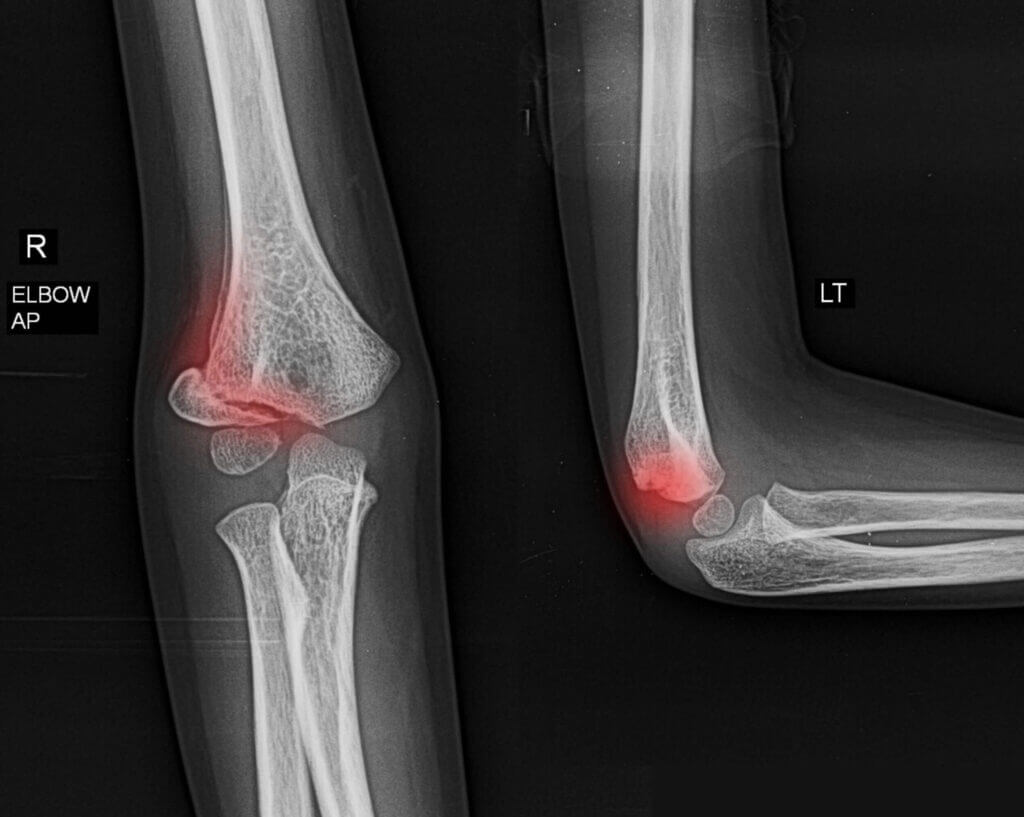

Common Causes of Elbow Pain

• Strains and Sprains – Injuries to muscles or ligaments due to overuse or trauma

• Fractures and Dislocations – Breaks or misalignment of elbow bones often caused by falls or accidents

• Tennis Elbow (Lateral Epicondylitis) – Overuse injury causing pain on the outer elbow

• Golfer’s Elbow (Medial Epicondylitis) – Overuse injury causing pain on the inner elbow

• Arthritis – Inflammation and degeneration of elbow joint tissues

These conditions can cause pain, swelling, stiffness, weakness, and limited range of motion.

Our skilled medical team offers thorough evaluations using on-site X-rays and ultrasound imaging to accurately diagnose elbow conditions. Personalized treatment plans include: